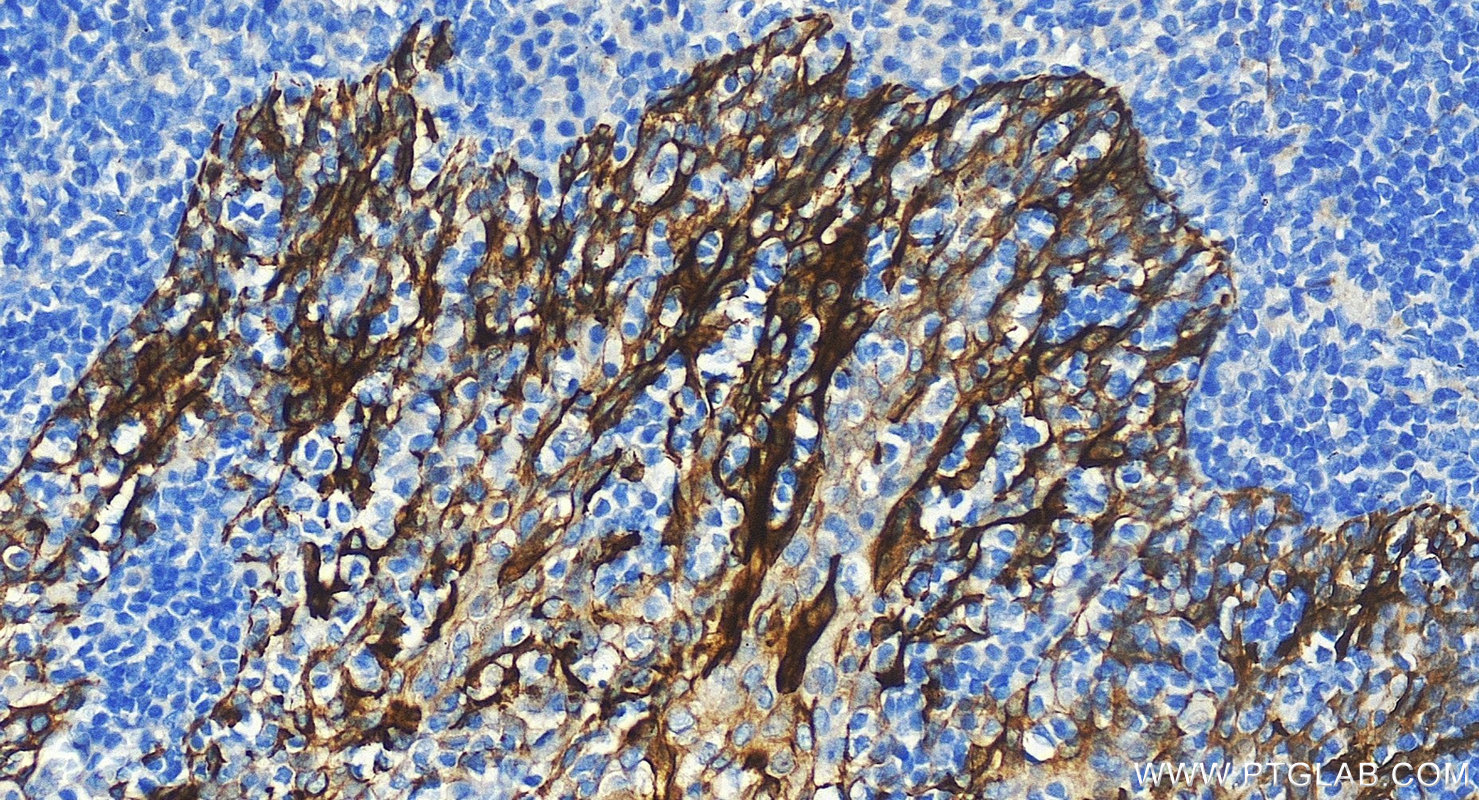

| Positive IHC detected in | human tonsillitis tissue, human appendicitis tissue, human bowen disease tissue, human breast cancer tissue, human colon tissue, human liver tissue, human renal cell carcinoma tissue Note: suggested antigen retrieval with TE buffer pH 9.0; (*) Alternatively, antigen retrieval may be performed with citrate buffer pH 6.0 |

Cytokeratin 8 (CK8) is a protein that belongs to the cytokeratin family, which is a group of structural proteins found in the intracytoplasmic cytoskeleton of epithelial cells. CK8 forms intermediate filaments within the cytoplasm of simple epithelial cells, typically as a dimer with cytokeratin 18 (CK18). These filaments provide a stabilizing framework that helps determine cell shape and enables cells to cope with mechanical stress. CK8/CK18 filaments also serve as a mesh of "paths" for signaling molecules, metabolites, and pathogens to travel within the cell in an organized manner. CK8 is expressed in various epithelial tissues and is particularly associated with glandular and simple epithelia. Its expression is also a significant marker in several types of cancer, including lung and esophageal cancer, where it can indicate tumor progression and poor prognosis.